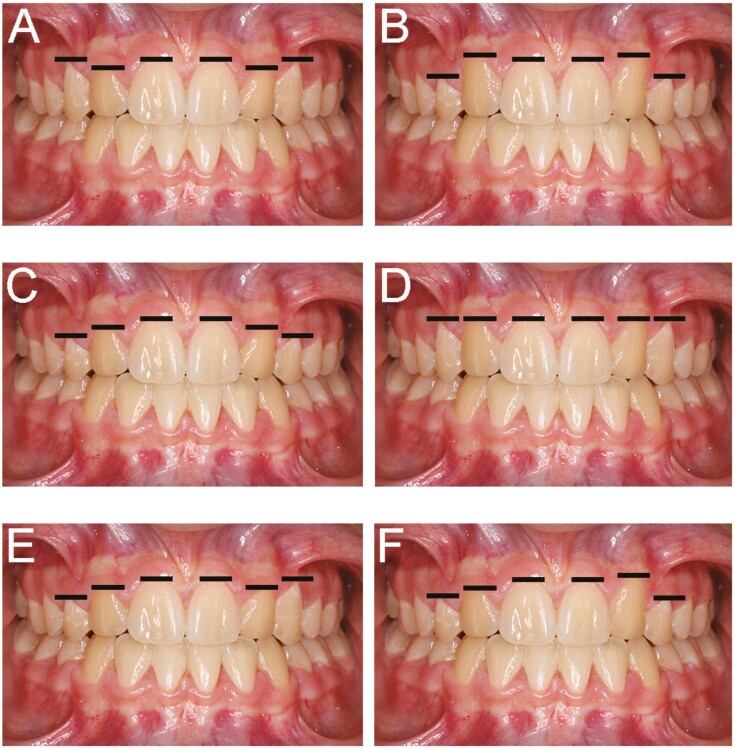

Material and methods: Images of a case treated with space closure and bilateral canine substitution were digitally modified to create gingival margin height variation for the substituted lateral incisors and canines. Six variations were created, including one conforming to accepted norms for anatomic gingival margin heights. Lay people represented by parents of orthodontic patients ranked the images based on aesthetics, with data analysed statistically using linear models at 5%.

Results: One hundred and twenty responders were included (median age 48.0 years), 50% male and 81.7% Caucasian, with 87% able to provide specific preferences. In absolute terms, the highest-ranking [image C] had substituted lateral incisor gingival margins below the central incisors (considered normal) but substituted canine margins symmetrically below the substituted lateral incisors (considered to be too low); followed by [image D] with symmetrically level gingival margins; and [image F] with asymmetric substituted lateral incisor margins and substituted canine margins symmetrically too low. The lowest-ranked [image E] had normal substituted lateral incisor margins but asymmetric substituted canine margins. Image C was most often ranked first (29.8% of responders) and image E last (22.1%). After adjusting for potential confounding effects, image E received the worse scores.

Conclusions: Anatomic norms for gingival margin height in absent maxillary lateral incisor-canine substitution do not correlate with the highest-ranking aesthetic choices of a lay population. Lateral incisor gingival margins symmetrically below the central incisors and substituted canine margins symmetrically below these ranked highest. Vertical asymmetry in the substituted canine position was considered the least aesthetic.